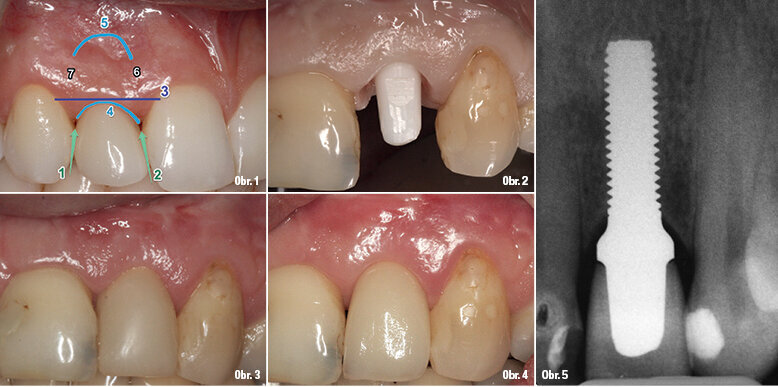

V naší ordinaci používáme zirkon od roku 2004. Stejně jako v každé zubní ordinaci jsou tím, co se nakonec počítá, funkční a estetické výsledky, spolu s bezpečností materiálu. Výsledky se musí blížit, splňovat nebo překonávat očekávání pacientů. My používáme k posouzení estetických výsledků Fürhauserovo skóre růžové estetiky (PES) (obr. 1).4

Případ 1 (2008)

Tento případ je předložen jako ukázka PES. Zabránili jsme tomu, aby gingiva přerostla přes krček implantátu dobře dosedající provizorní korunkou, která krček implantátu překrývala. To vedlo k atraumatické proceduře formování gingivy a cementování korunky. Oblý schůdek představoval s ohledem na vestibulární estetiku a cementování korunky zvláštní výzvu. Hloubka zavedení byla koronální po horní část závitu.

Implantologie s jednodílnými implantáty vyžaduje pro protetické ošetření zvláštní podmínky, lze ošetřit pouze část potřebných indikací (obr. 2–5). Dnes můžeme jít dál díky použití zirkonových implantátů pro různé indikace vyráběných firmou Z-Systems (obr. 6).5